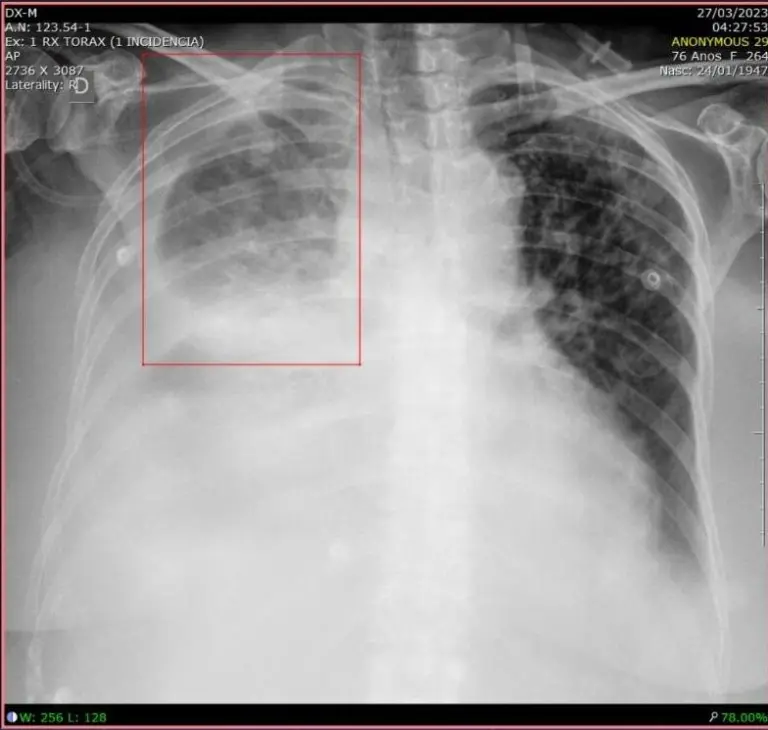

Rayos X de pulmón con IA para radiología

La neumonía es una infección pulmonar responsable de más de 600 mil internaciones por año en el Sistema Único de Salud (SUS) de Brasil.

El diagnóstico de neumonía en una radiografía de tórax involucra especialistas capacitados y el cruce de información de historial clínico, signos vitales y estudios de laboratorio.

Para ayudar en este desafío, algoritmos de machine learning pueden detectar manchas de opacidad pulmonar (derrame pleural, cardiomegalia, edema pulmonar agudo, nódulos pulmonares) y señalarlas en recuadros para evaluación médica, especificando la ubicación y el tamaño de cualquier infección detectada.

Esto aporta productividad para los médicos en la toma de decisiones de tratamiento (neumonía leve versus neumonía grave, por ejemplo) y también retroalimenta el sistema a medida que los médicos validan o descartan el hallazgo clínico señalado por la computadora.